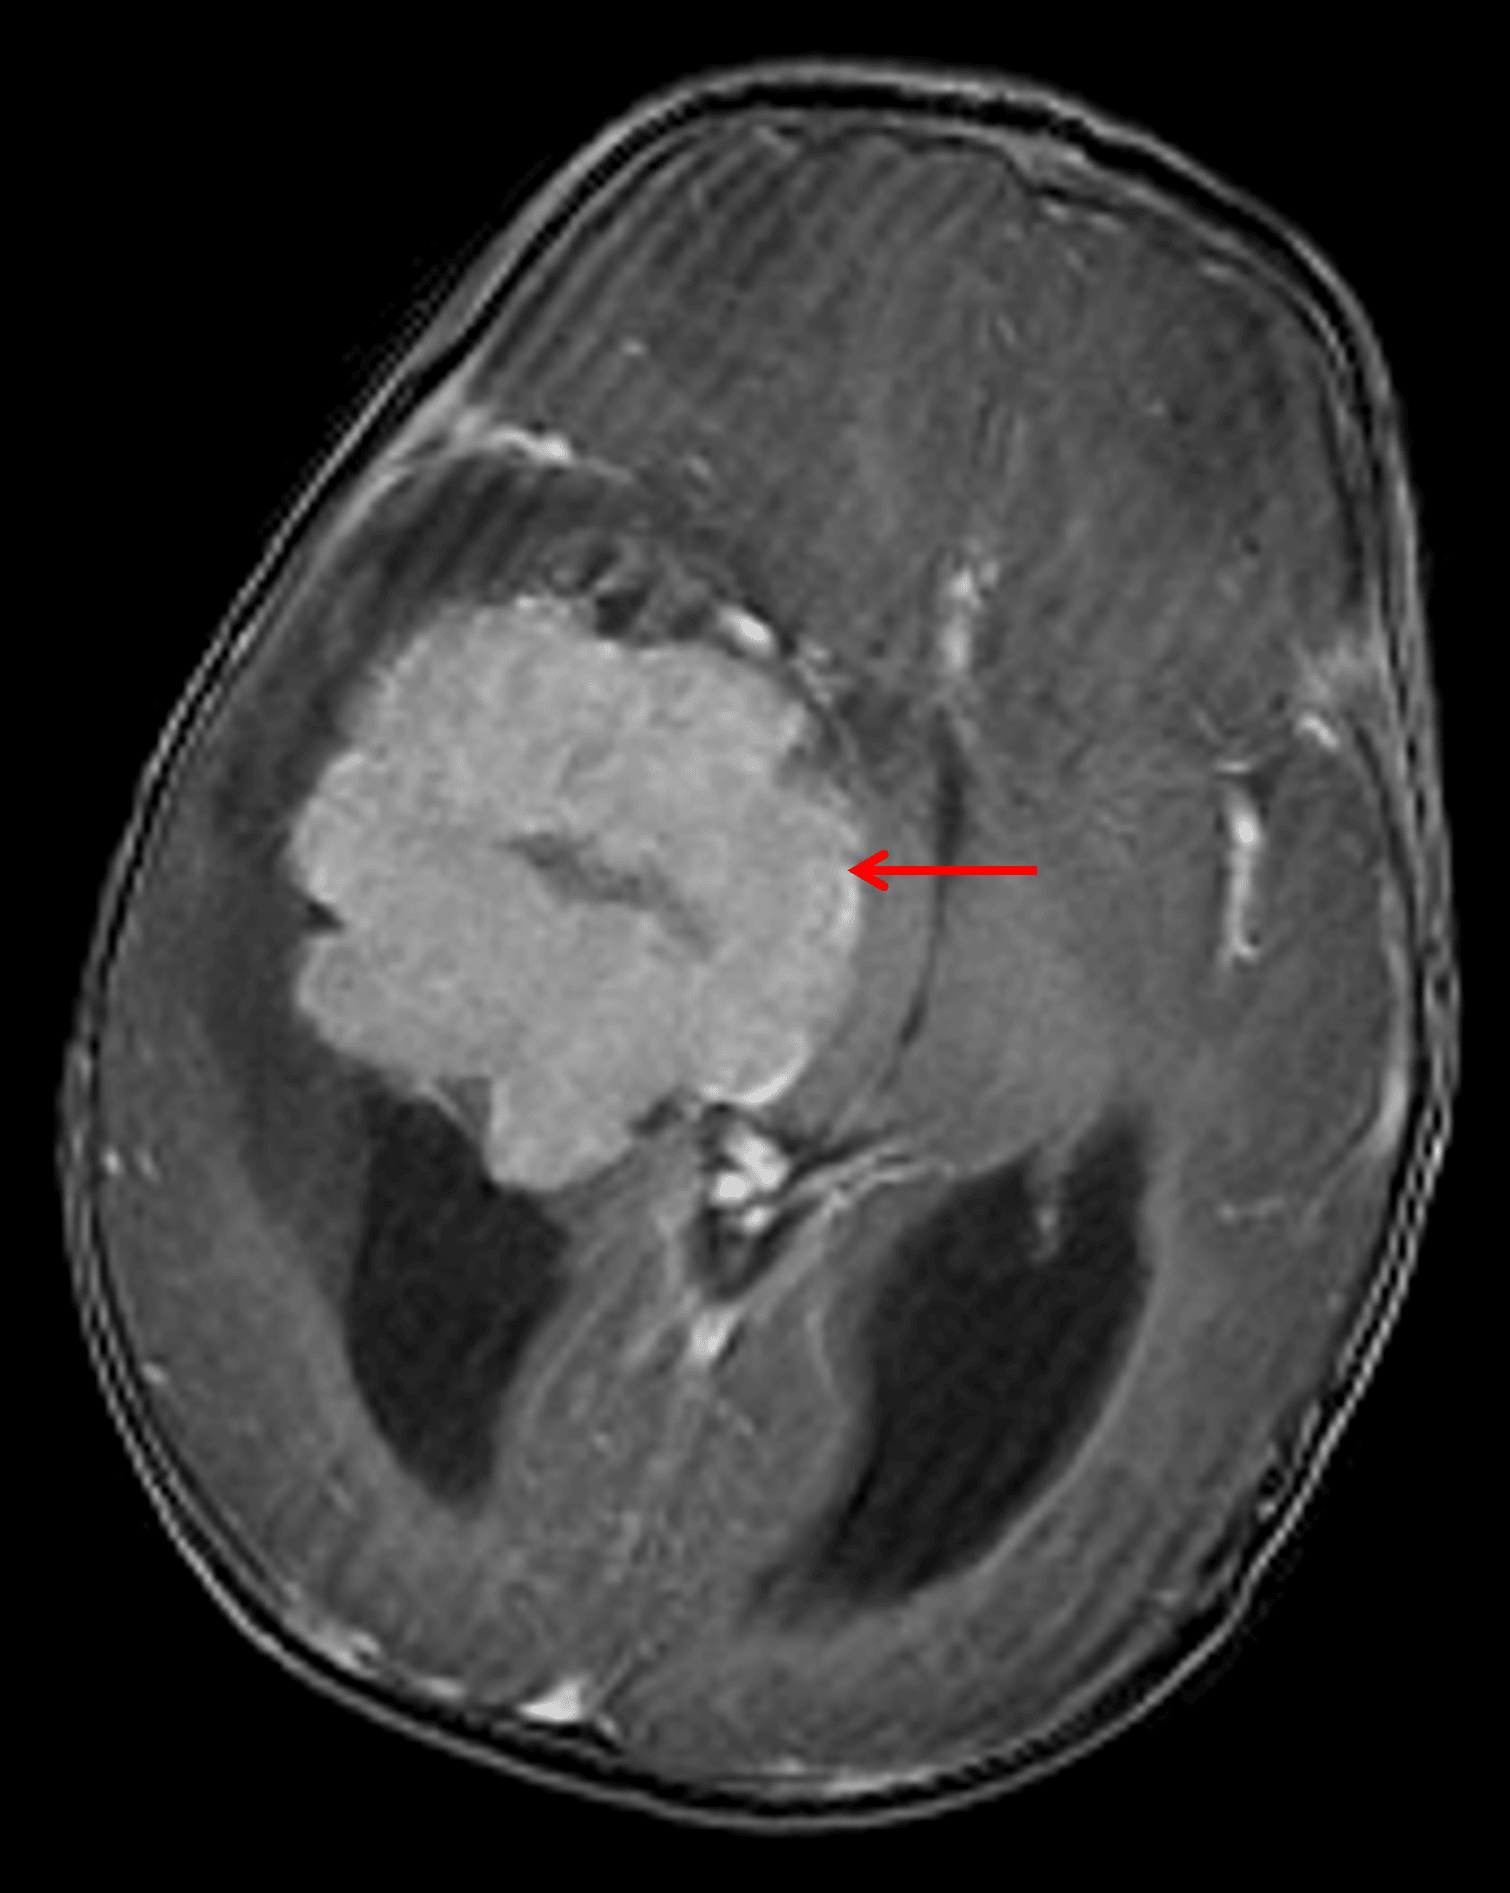

• Avidly enhancing mass with lobulated contours centered in the temporal horn of the right lateral ventricle measuring 6.5 x 5.5 x 6 cm, inseparable from the choroid plexus

Avidly enhancing mass centered in the temporal horn of the right lateral ventricle (red arrow), consistent with a choroid plexus tumor.

• Tumor bulges into the adjacent cerebral parenchyma in multiple locations

• Cystic collections along the tumor margins may represent peritumoral cysts and/or isolated ventricular components

• Associated mass effect with 1.5 cm right-to-left midline shift, effacement of the third ventricle, and crowding of the basal cisterns with mass effect on the midbrain